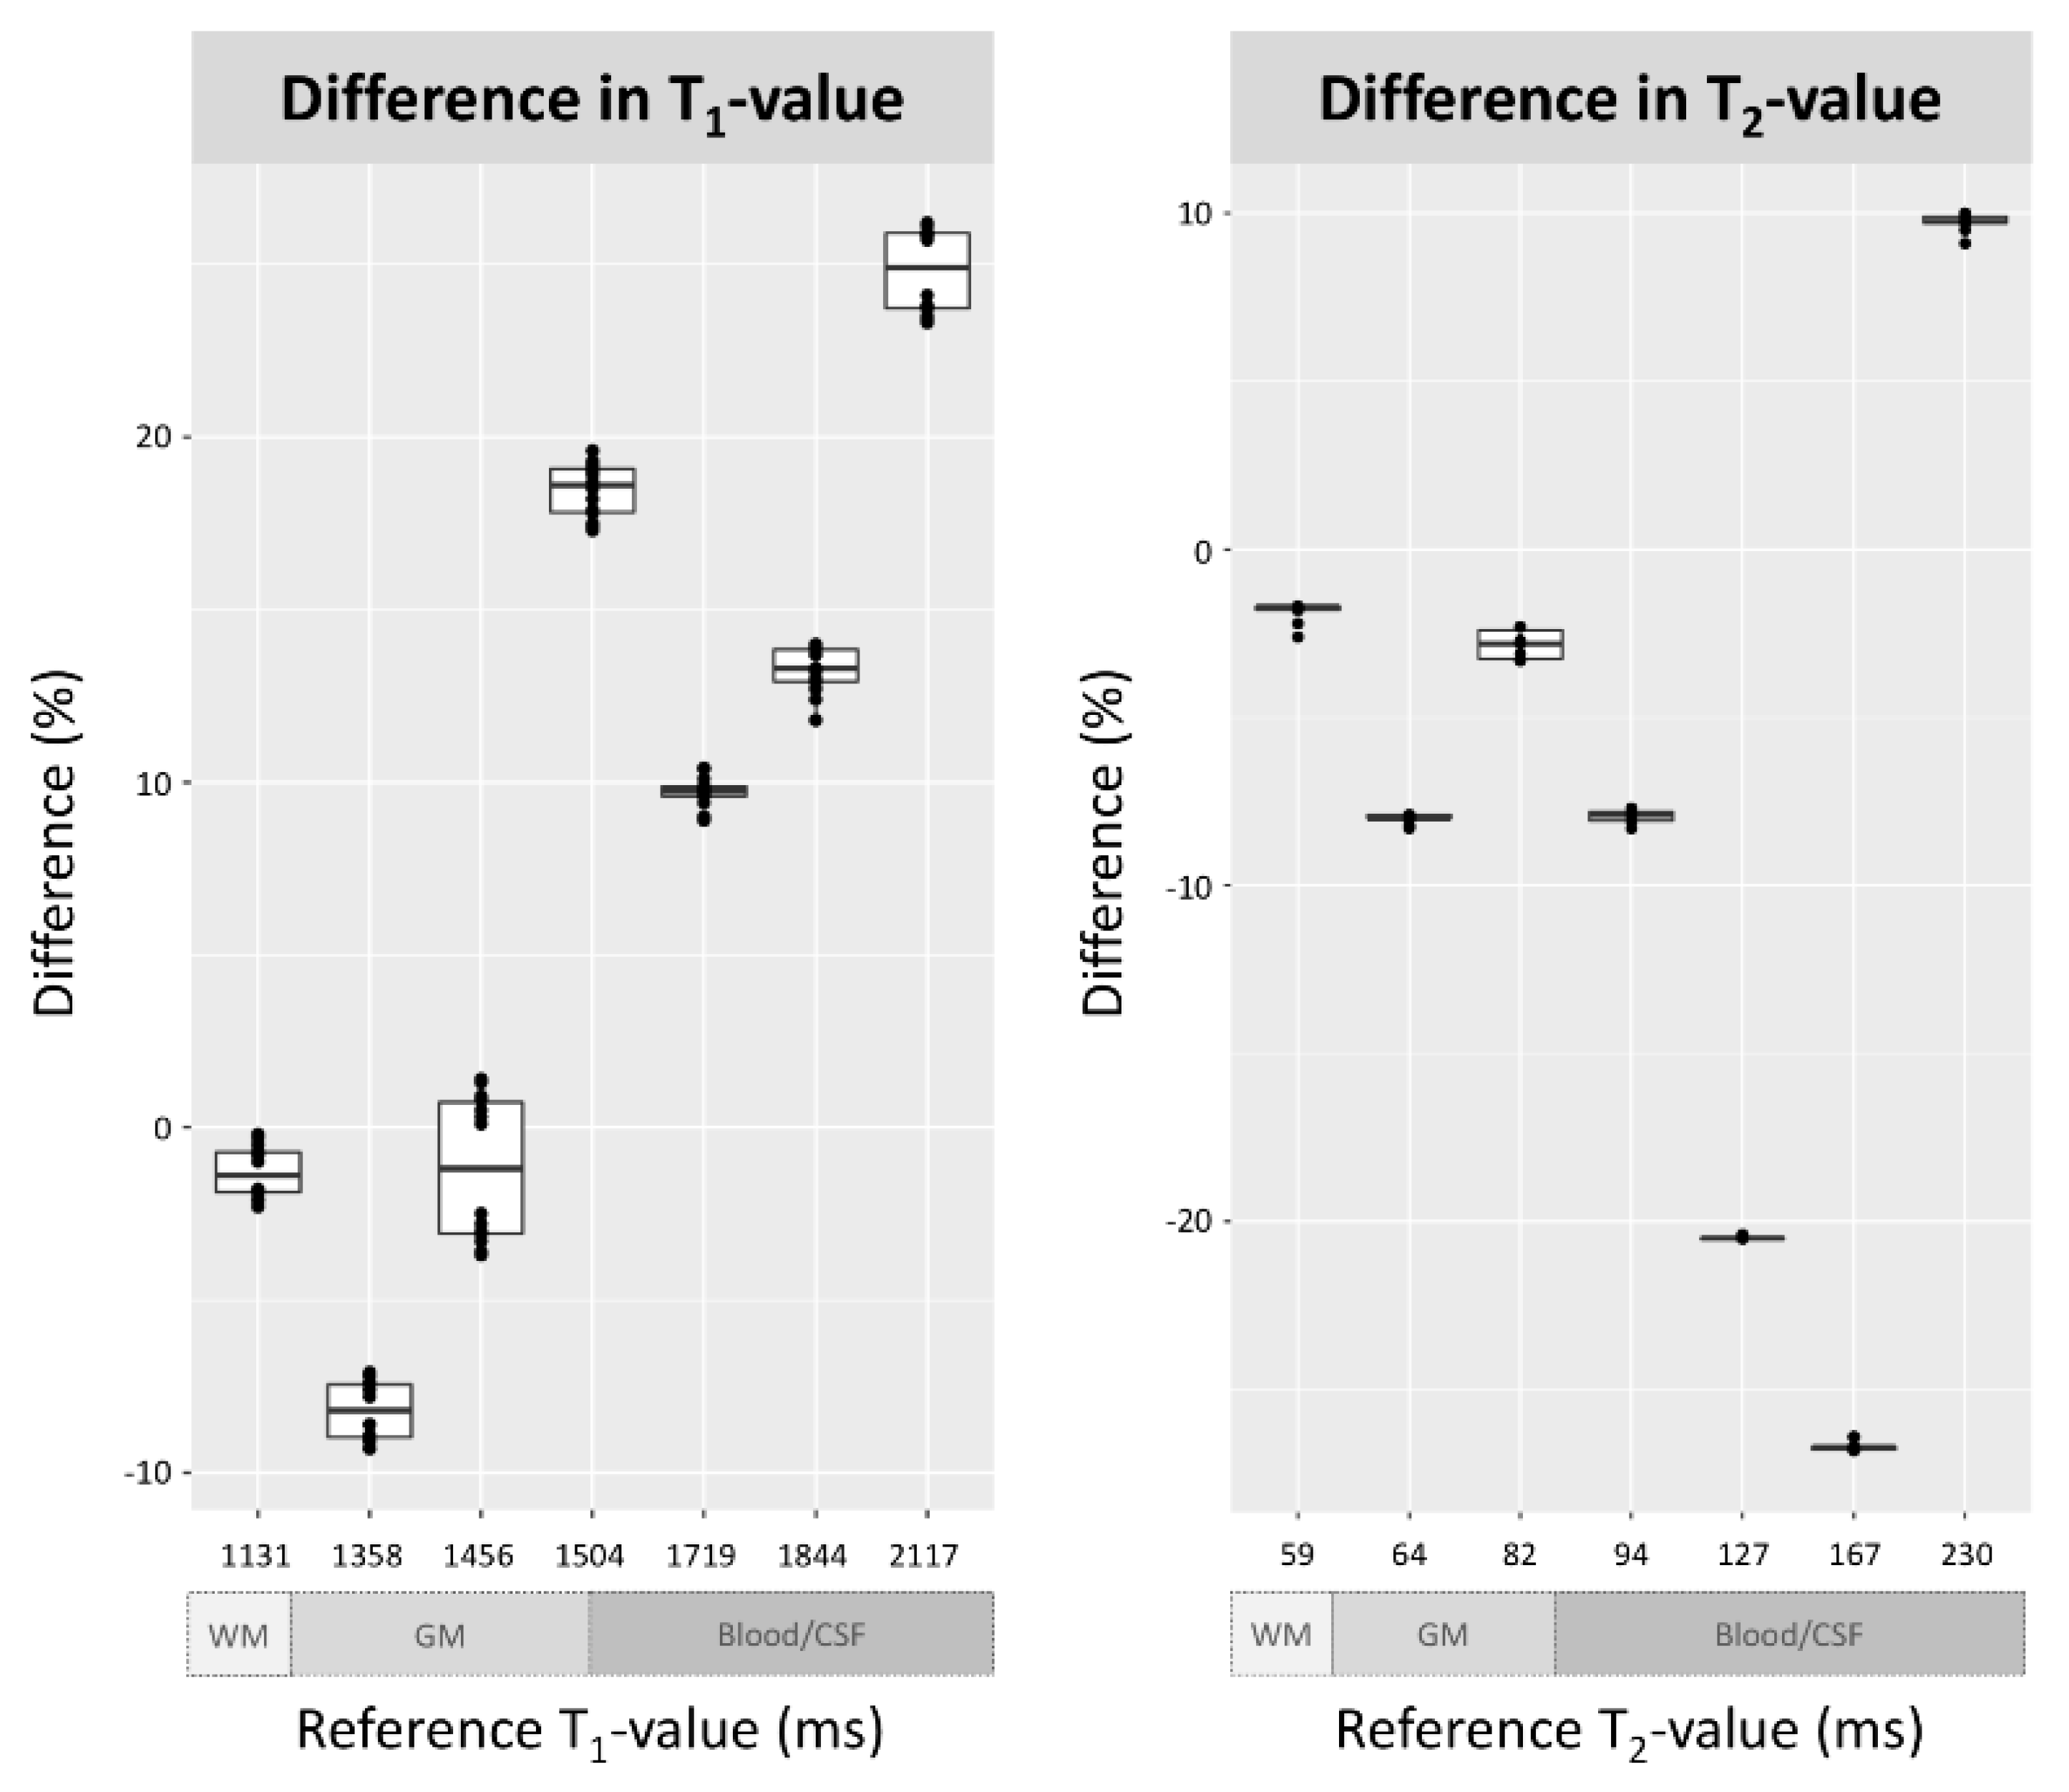

3.1. Phantom Evaluation

3.2. Participant Evaluation

4. Discussion